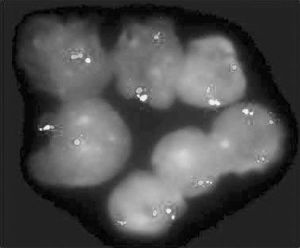

(2)體徵:主要表現為臟器浸潤。90%患者脾臟腫大程度不一,肋下可及至巨脾伸延至盆腔質硬常有明顯切跡。脾栓塞時脾區可觸及摩擦感或聞及摩擦音。可有輕到中度肝臟腫大,淋巴結腫大少見胸骨常有壓痛,以胸骨柄的下端為著眼底視網膜浸潤可見到視網膜血管迂迴擴張並可見呈片狀的出血斑以及白色浸潤中心